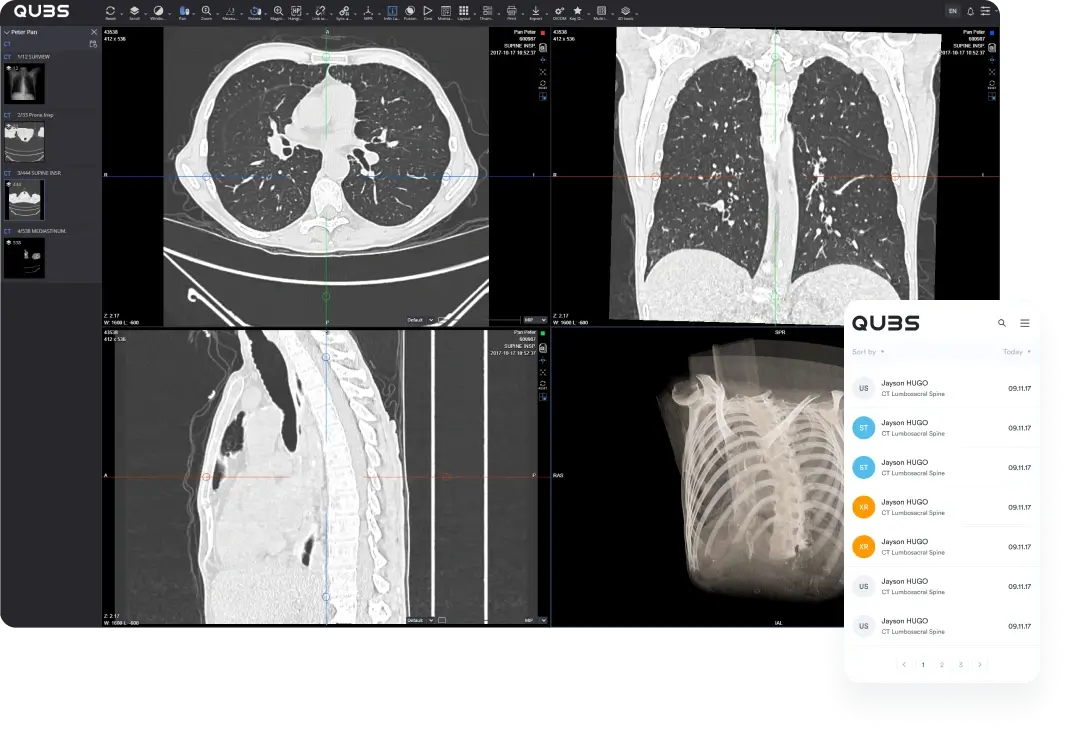

Open studies instantly

with a zero-footprint

viewer

Give radiologists and referrers browser-based access to current studies and priors without installing heavy desktop software at every location.